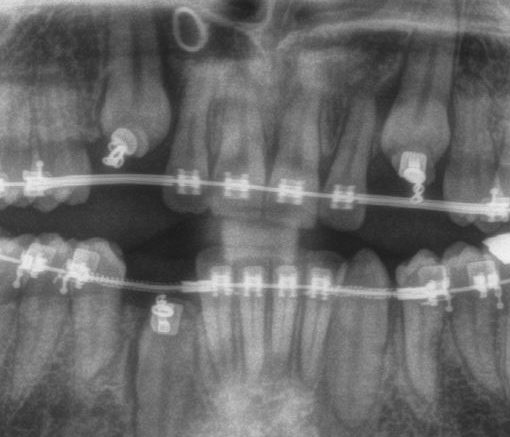

Conventional Braces